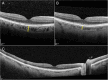

Case presentation: A 69-year-old male was diagnosed with a choroidal melanoma, measuring 13.3 mm in diameter and 5.8 mm in thickness, in the left eye. Seven years after iodine-125 plaque brachytherapy, systemic imaging identified a solitary liver metastasis, which was laparoscopically resected. About one year later, two new liver metastases were detected. The patient was HLA-A*02:01 positive and started on tebentafusp. Except for transient fever, rash, and pruritus after the first cycles, the therapy was well tolerated. Fourteen months after initiation of tebentafusp, fundoscopy revealed marked hypopigmentation of both fundi and depigmentation of the regressed tumour in left eye. There were no signs of intraocular inflammation in either eye. Upon retrospective review of fundus photographs taken from baseline, the progressive fundus hypopigmentation and depigmentation of the tumour remnants first appeared after the initiation of immunotherapy. A corresponding evaluation of the optical coherence tomography scans of the previously untreated right eye revealed a significant reduction in central choroidal thickness over the same period. Full-field electroretinography demonstrated normal responses in the right eye and attenuated responses in the left eye. Screening for paraneoplastic antibodies was negative. During treatment, he also developed poliosis of the eyebrows and cilia, along with depigmented skin macules and patches. At the last visit, 11 years after the initial diagnosis and 26 months after starting tebentafusp, a repeat CT confirmed stable liver metastases with no new lesions. Both fundi appeared hypopigmented, and best corrected visual acuity was 1.0 in the right eye and hand movements in the left eye.

Conclusions: Tebentafusp therapy can lead to diffuse fundus hypopigmentation and choroidal thinning, similar to what has been reported after immune checkpoint inhibition. The progressive choroidal hypopigmentation, without evidence of associated intraocular inflammation, indicates that glycoprotein 100, the target antigen of tebentafusp, is also expressed by normal choroidal melanocytes.